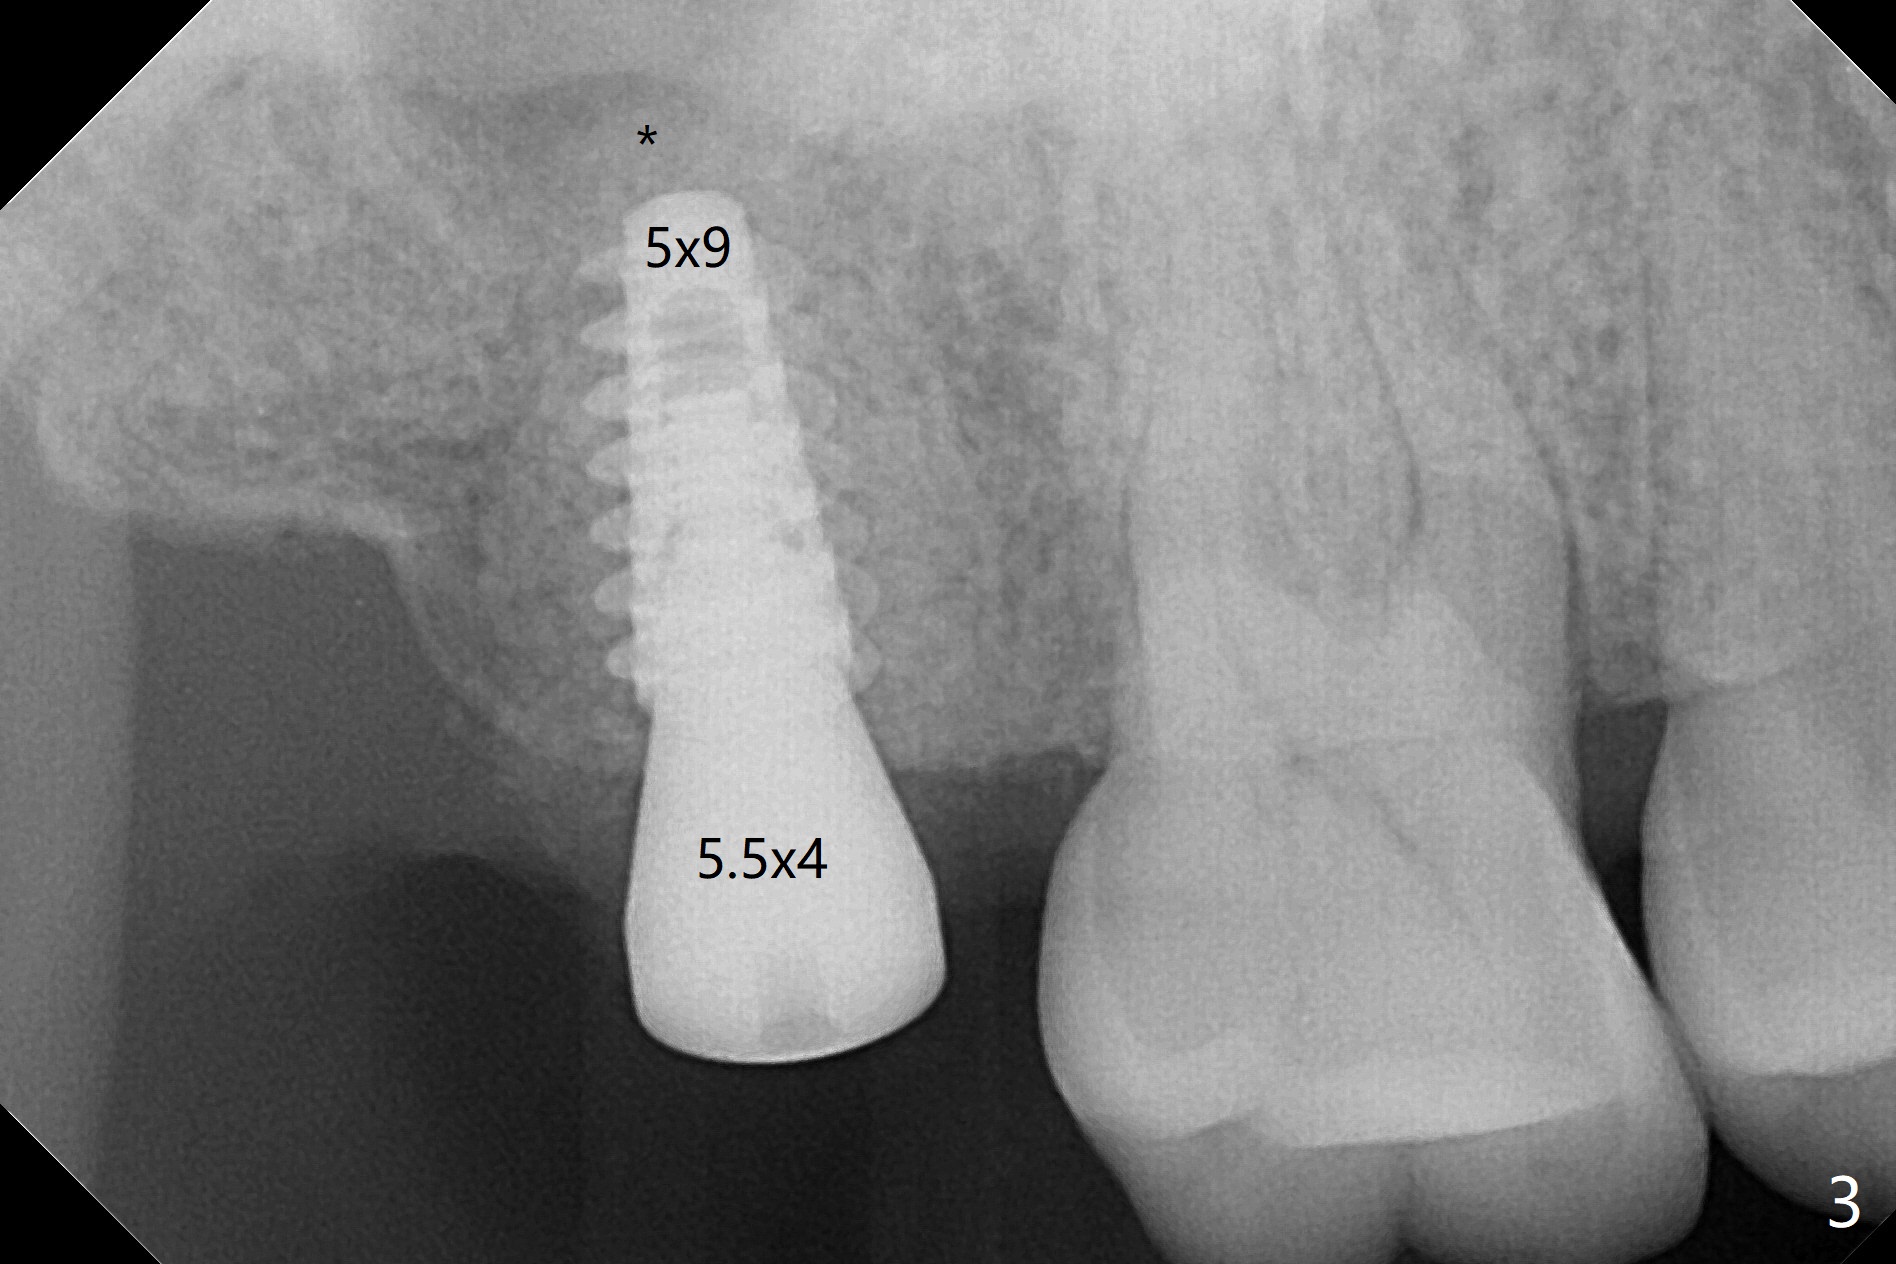

术前CT显示右上7牙槽骨不平,可能造成植体偏移,腭侧,远中螺纹暴露,为了方便导板种植后植骨,切开翻瓣,牙槽骨外形与CT检查一致,不过1.5毫米offset牙槽嵴磨平钻头所形成钻洞正常,除了骨质密度高之外,术中临床和射线检查发现植体方向和种植水平与设计一致,没有偏移(图一至三),最后只有腭侧一个螺纹暴露,放置愈合基台后,放入粘性骨粉,覆盖PRF膜,近中,远中各缝合一针,其余使用牙周胶水关闭伤口。不偏位可能原因:使用1.5毫米offset,骨质密度高,两侧密度接近。术后一周远中伤口裂开(图四:*),近中,远中应该多缝合一针。术后三周伤口愈合。The implant threads are subcrestal 5 months postop (Fig.5).